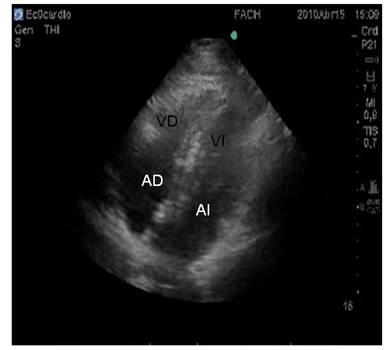

También se utilizaron visiones del eje apical en que se obtienen imágenes en 4 cámaras (ambas aurículas y ventrículos) y de 5 cámaras (ambas aurículas, ambos ventrículos y tracto de salida del ventrículo izquierdo) (Figura 2).

En nuestro estudio empleamos principalmente la ventana paraesternal izquierda y apical en 5 cámaras. (Figura 3)

Se colocó el transductor en la región paraesternal izquierda, entre la 3º y la 4º costilla. En este eje largo evaluamos el ventrículo izquierdo (VI), ventrículo derecho, aurícula izquierda y las válvulas mitral y aórtica. La medición fundamental que se realizó a este nivel fue el tracto de salida del VI, justo por debajo de la válvula aórtica Utilizando la ventana paraesternal izquierda se midió el diámetro del tracto de salida (la mitad del diámetro corresponde al radio = r) del ventrículo izquierdo y se le calculó su área.(Figura 4).